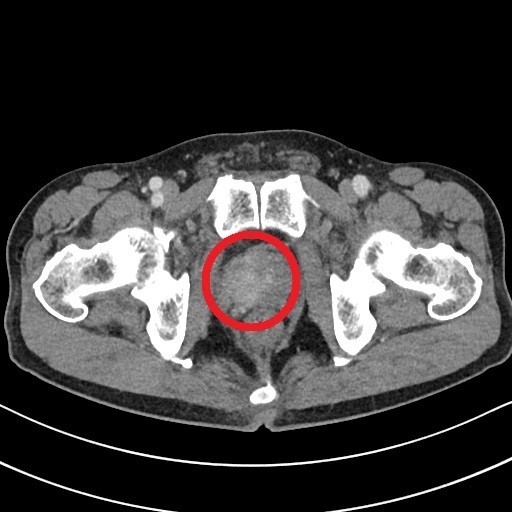

8. 골반통

골반 고통은 진행성 전립선암의 징후일 수 있어요. 고통은 일반적으로 옆구리, 배, 골반 부위에서 느껴지지만 암이 진행됨에 따라 뼈에서도 고통이 느껴질 수 있어요. 이런 부위에 고통이 있고 요로 감염 증상이 나타나면 의사를 내원해서 정확한 진단을 받는 것이 좋아요.